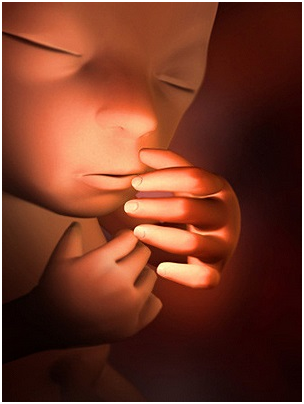

怀孕第16周现在你可以感到胎动啦,可别忘了把你第一次感到胎动的时间记下来哦!一定要抓住这段时...

怀孕第16周现在你可以感到胎动啦,可别忘了把你第一次感到胎动的时间记下来哦!一定要抓住这段时... -

怀孕第17周宝宝能听到你的声音了,尤其喜欢听到妈妈温柔的说话声。所以,现在可是胎教的最佳时期...

怀孕第17周宝宝能听到你的声音了,尤其喜欢听到妈妈温柔的说话声。所以,现在可是胎教的最佳时期... -